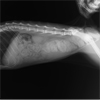

◆バーニーズ・マウンテンドッグ 6歳2カ月 メス(避妊済み) 35.8㎏

◆稟告 10日前から左後肢跛行